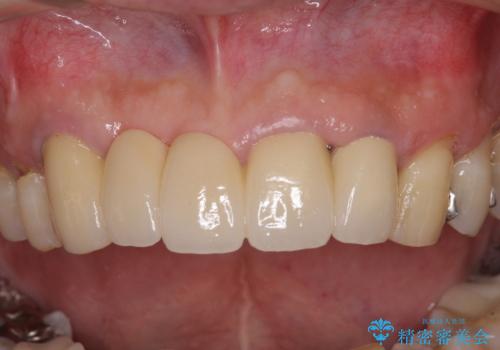

露出していた歯根や金属の縁が見えてしまい、人前で話すときの目線が気になっていらっしゃいましたが、歯肉の位置に縁を合わせてことで自然な仕上がりとなりました。

露出していた歯根が覆われるため、歯冠が長く見えてしまうことが懸念されましたが特に気になることはなく、患者様には大変満足していただきました。